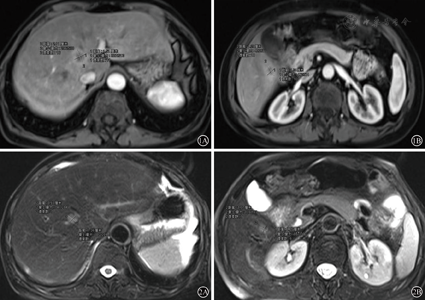

患者58岁女性,以"大便不成形8月余,加重4月"为主诉入院,直肠指检:距肛门5 cm可触及一质硬包块,累及管腔全周,不易推动,退出后见指套血染;肠镜:距肛5 cm可见一巨大新生物致管腔狭窄。病理活检示:(距肛5 cm)查见腺癌。腹部增强CT:直肠中、下段管壁增厚,多系肿瘤病变,局部系膜淋巴结增大增多,左侧侧方淋巴结肿大,边缘强化明显;肝右叶结节,多系转移;胸部CT平扫未见异常;上腹部MRI发现肝脏两枚结节大小分别为:2.1 cm×1.5 cm,1.3 cm×1.2 cm(见图1A、图1B)。肿瘤标志物:癌胚抗原13.47 ng/ml(正常<3.4 ng/ml),甲胎蛋白:2.39 ng/ml(正常<8.0 ng/ml)。初步诊断:直肠癌同时性肝转移(cT4N+M1,Ⅳ期)

经过4周期mFOLFOX6方案化疗及盆腔局部短程放疗后,肝转移灶分别缩小至约1.3 cm×0.9 cm,1.0 cm×0.75 cm,(见图2A、图2B),癌胚抗原下降到2.29 ng/ml(正常<3.4 ng/ml),环周切缘转为阴性。再次MDT讨论后,行腹腔镜辅助直肠癌根治性前切除、左侧侧方淋巴结清扫、预防性造瘘、肝左内叶肿瘤射频消融、肝右叶肿瘤局部切除术。